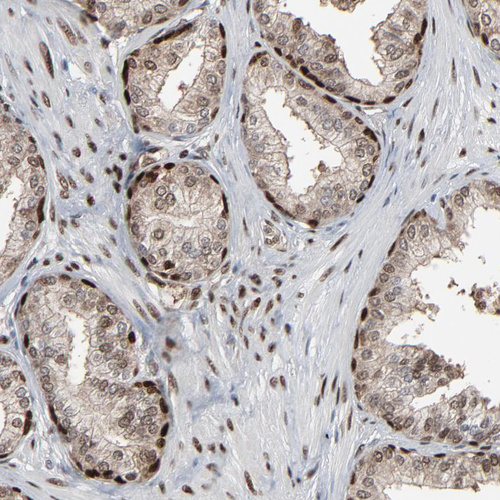

Immunohistochemical staining of human endometrium shows moderate nuclear positivity in glandular and stromal cells.